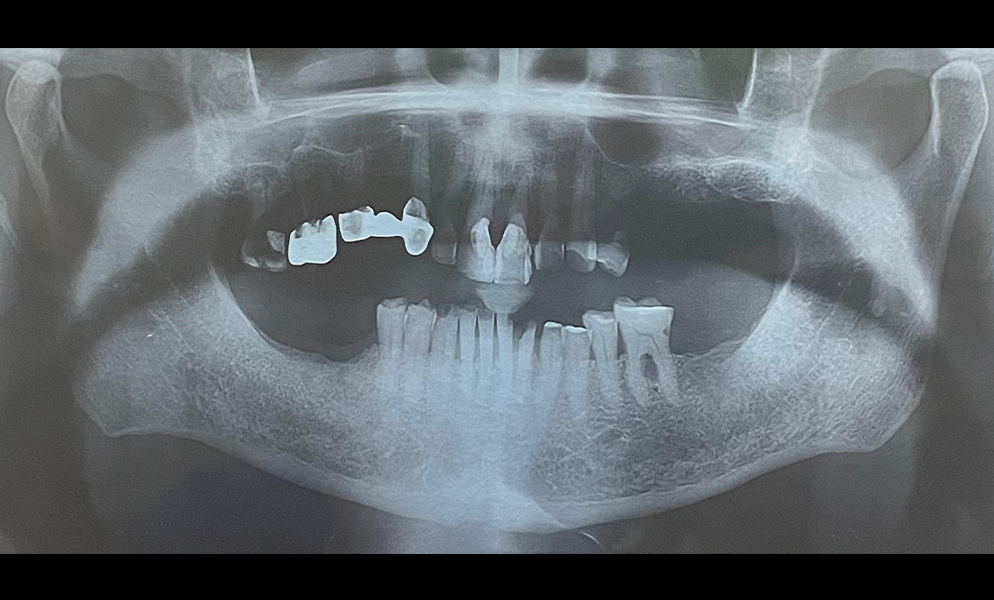

| Before | After |

![]() |

| Full-mouth reconstruction with short dental implant (Bicon, USA)-supported prosthesis | |